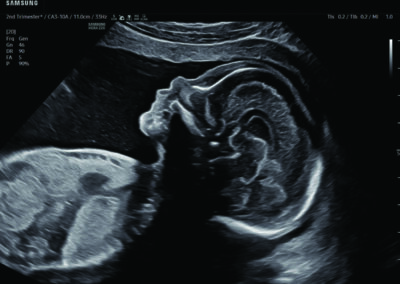

Comprehensive, advanced and expert MFM care for high-risk pregnancies

- Fetal anomalies